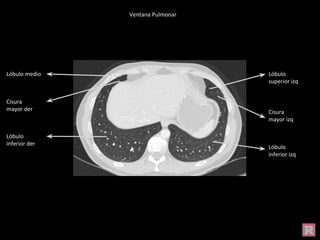

Ventana Pulmonar

Bronquio

fuente der

fuente Izq

Cisura

mayor izq

Lóbulo

inferior izq

superior izq

superior der

inferior der

mayor der